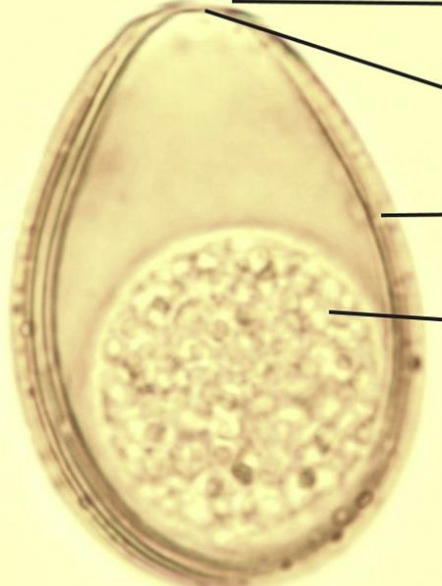

ID

Eimeria (leuckarti)